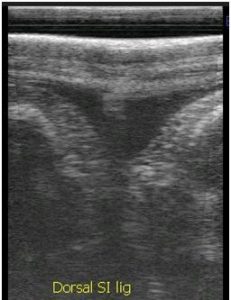

- Diagnostic imaging- radiography or ultrasound

- Radiography, ultrasound

A high quality ultrasound is a very valuable imaging tool for evaluating and diagnosing a wide range of conditions primarily but not limited to soft tissue. Musculoskeletal structures such as tendons, ligaments, joints, muscles and bone surfaces may be evaluated for signs of injury or infection. Once an injury is found, ultrasound allows for monitoring healing progress. It can be used for ultrasound guided injections of structures such as the sacroiliac and cervical joints. Ultrasound can aid in diagnosing the cause of colic and other abdominal conditions as well as conditions of the thorax such as pleuropneumonia and lung abscesses. Another very common use of ultrasonography is to monitor reproductive cycles and pregnancy in the broodmare.